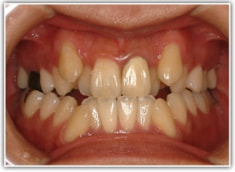

セファロ分析結果:上顎の劣成長と下顎の過成長が認められる値が出ています。重度の叢生といえます。

骨格的な下顎前突の傾向は強くはありませんが、歯牙の状態によって反対咬合が認められます。LowTongue(低位舌)もあります。

顔面の幅径はかなり狭い傾向にあります。

修復歯、補綴歯もあります。下顎8番が水平埋伏しています。